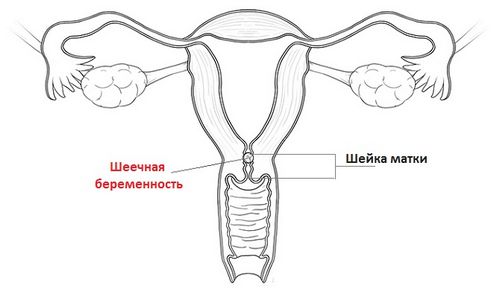

Як би сумно це не звучало, то частота виникнення позаматкового типу вагітності складає від 10 до 15% всіх випадків вагітності. Ускладнює ситуацію і те, що симптоматика позаматкової вагітності на ранніх термінах практично ідентична з симптомами фізіологічної вагітності.

Для позаматкового типу вагітності характерно уповільнене наростання концентрації ХГЛ, що визначається при динамічному контролі за допомогою спеціальних тестів-смужок.

Тести-смужки, а також касетні тести на визначення вагітності дуже схожі за своїм принципом дії. Позаматкова вагітність в даному випадку буде виражатися у вигляді двох смужок, одна з яких буде менш яскрава і навіть бліда. Позитивним тест на вагітність при позаматкової вагітності є тільки в разі повторного проведення тесту через 7 днів. Причиною такої блідості є повільне наростання концентрації ХГЛ в організмі жінки.